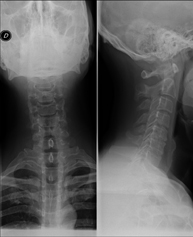

Técnica mediante la cual, utilizando rayos X, se obtienen imágenes del cavum para su estudio. Indicaciones: dificultad respiratoria, anginas de repetición en lactantes y niños. - RX Columna cervical

Técnica mediante la cual, utilizando rayos X, se obtienen imágenes de la columna cervical para su estudio. Indicaciones: traumatismo, contractura cervical, dolor articular. - RX Huesos propios nasales

- Cervical spine X-ray

This technique uses X-ray rendered imaging for examining the cervical spine. Indicated for: trauma, cervical pain.